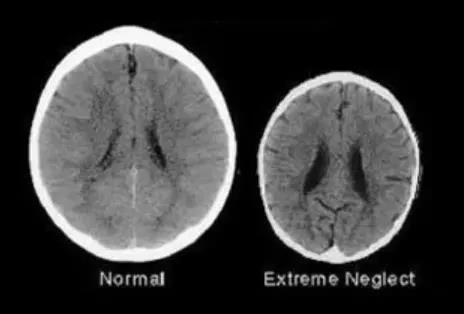

最終,孩子長(zhǎng)期處于恐懼的壞境中,大腦的發(fā)育就會(huì)更加遲緩。科學(xué)家曾經(jīng)做過(guò)一個(gè)實(shí)驗(yàn),他們分別找了兩個(gè)3歲左右大的孩子,一個(gè)孩子經(jīng)常被家長(zhǎng)鼓勵(lì)和贊美,另一個(gè)孩子則是常常被家長(zhǎng)指責(zé)、吼罵。

之后,科學(xué)家給這兩個(gè)孩子做了大腦掃描圖,發(fā)現(xiàn)經(jīng)常得到家長(zhǎng)夸獎(jiǎng)的孩子大腦要比經(jīng)常被家長(zhǎng)吼的孩子大一圈。

這意味著經(jīng)常被吼的那個(gè)孩子,腦容量相對(duì)較小,發(fā)育更加緩慢。